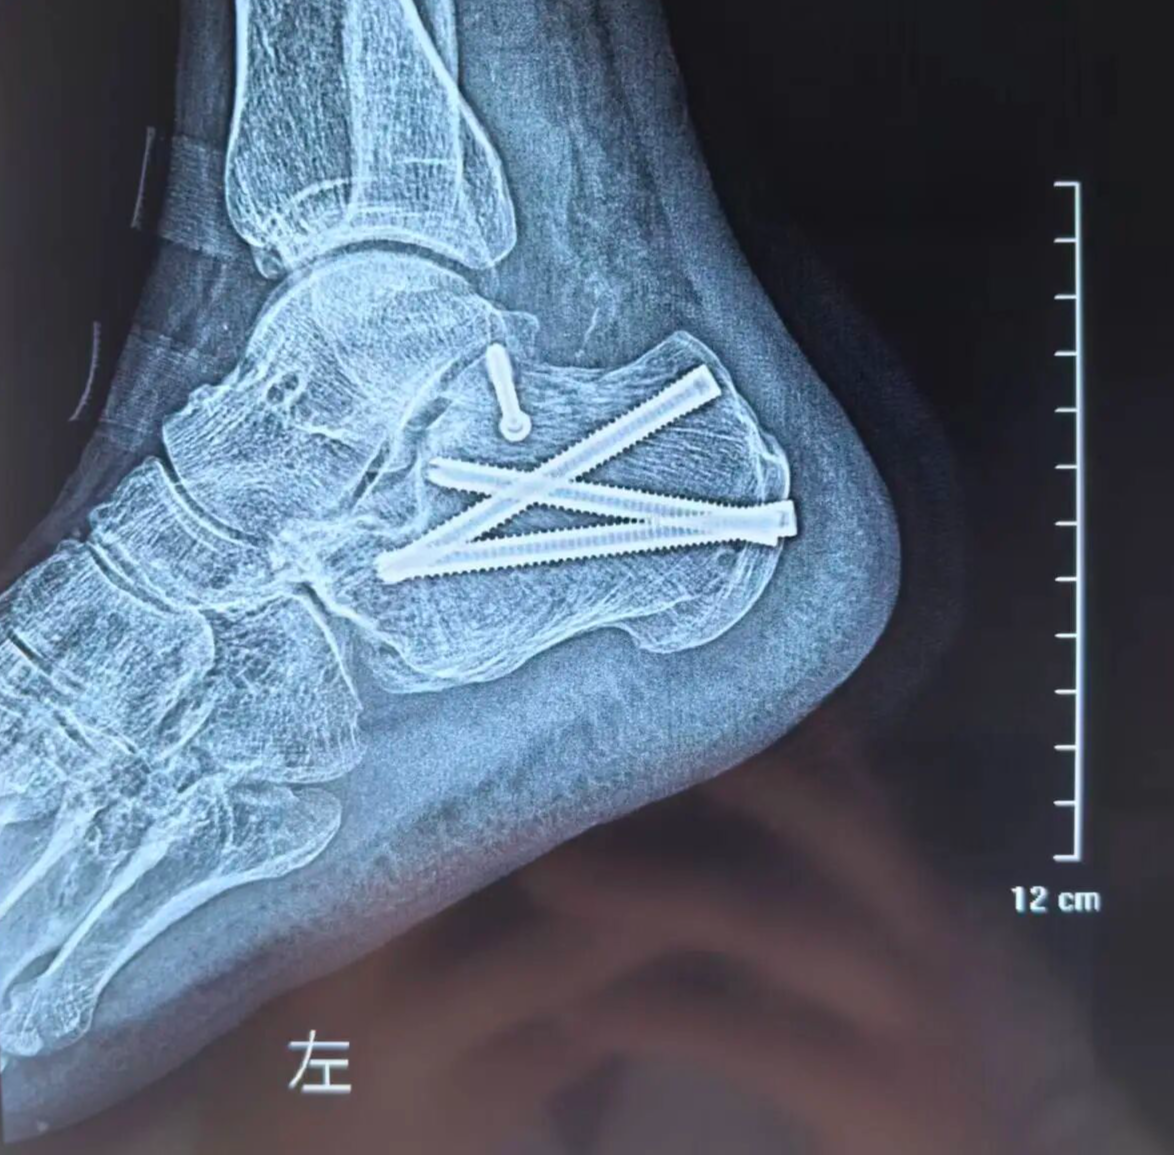

术后

日前,一名高处坠落伤致左侧跟骨粉碎性骨折的患者入院。骨三科团队经充分术前讨论,为其量身定制微创手术方案。术中在X光精准引导下,经皮撬拨复位骨折块,以空心螺钉稳固固定,出血极少、创伤小。术后患者恢复良好,早期即可开展功能锻炼,避免了传统大切口带来的并发症隐患。